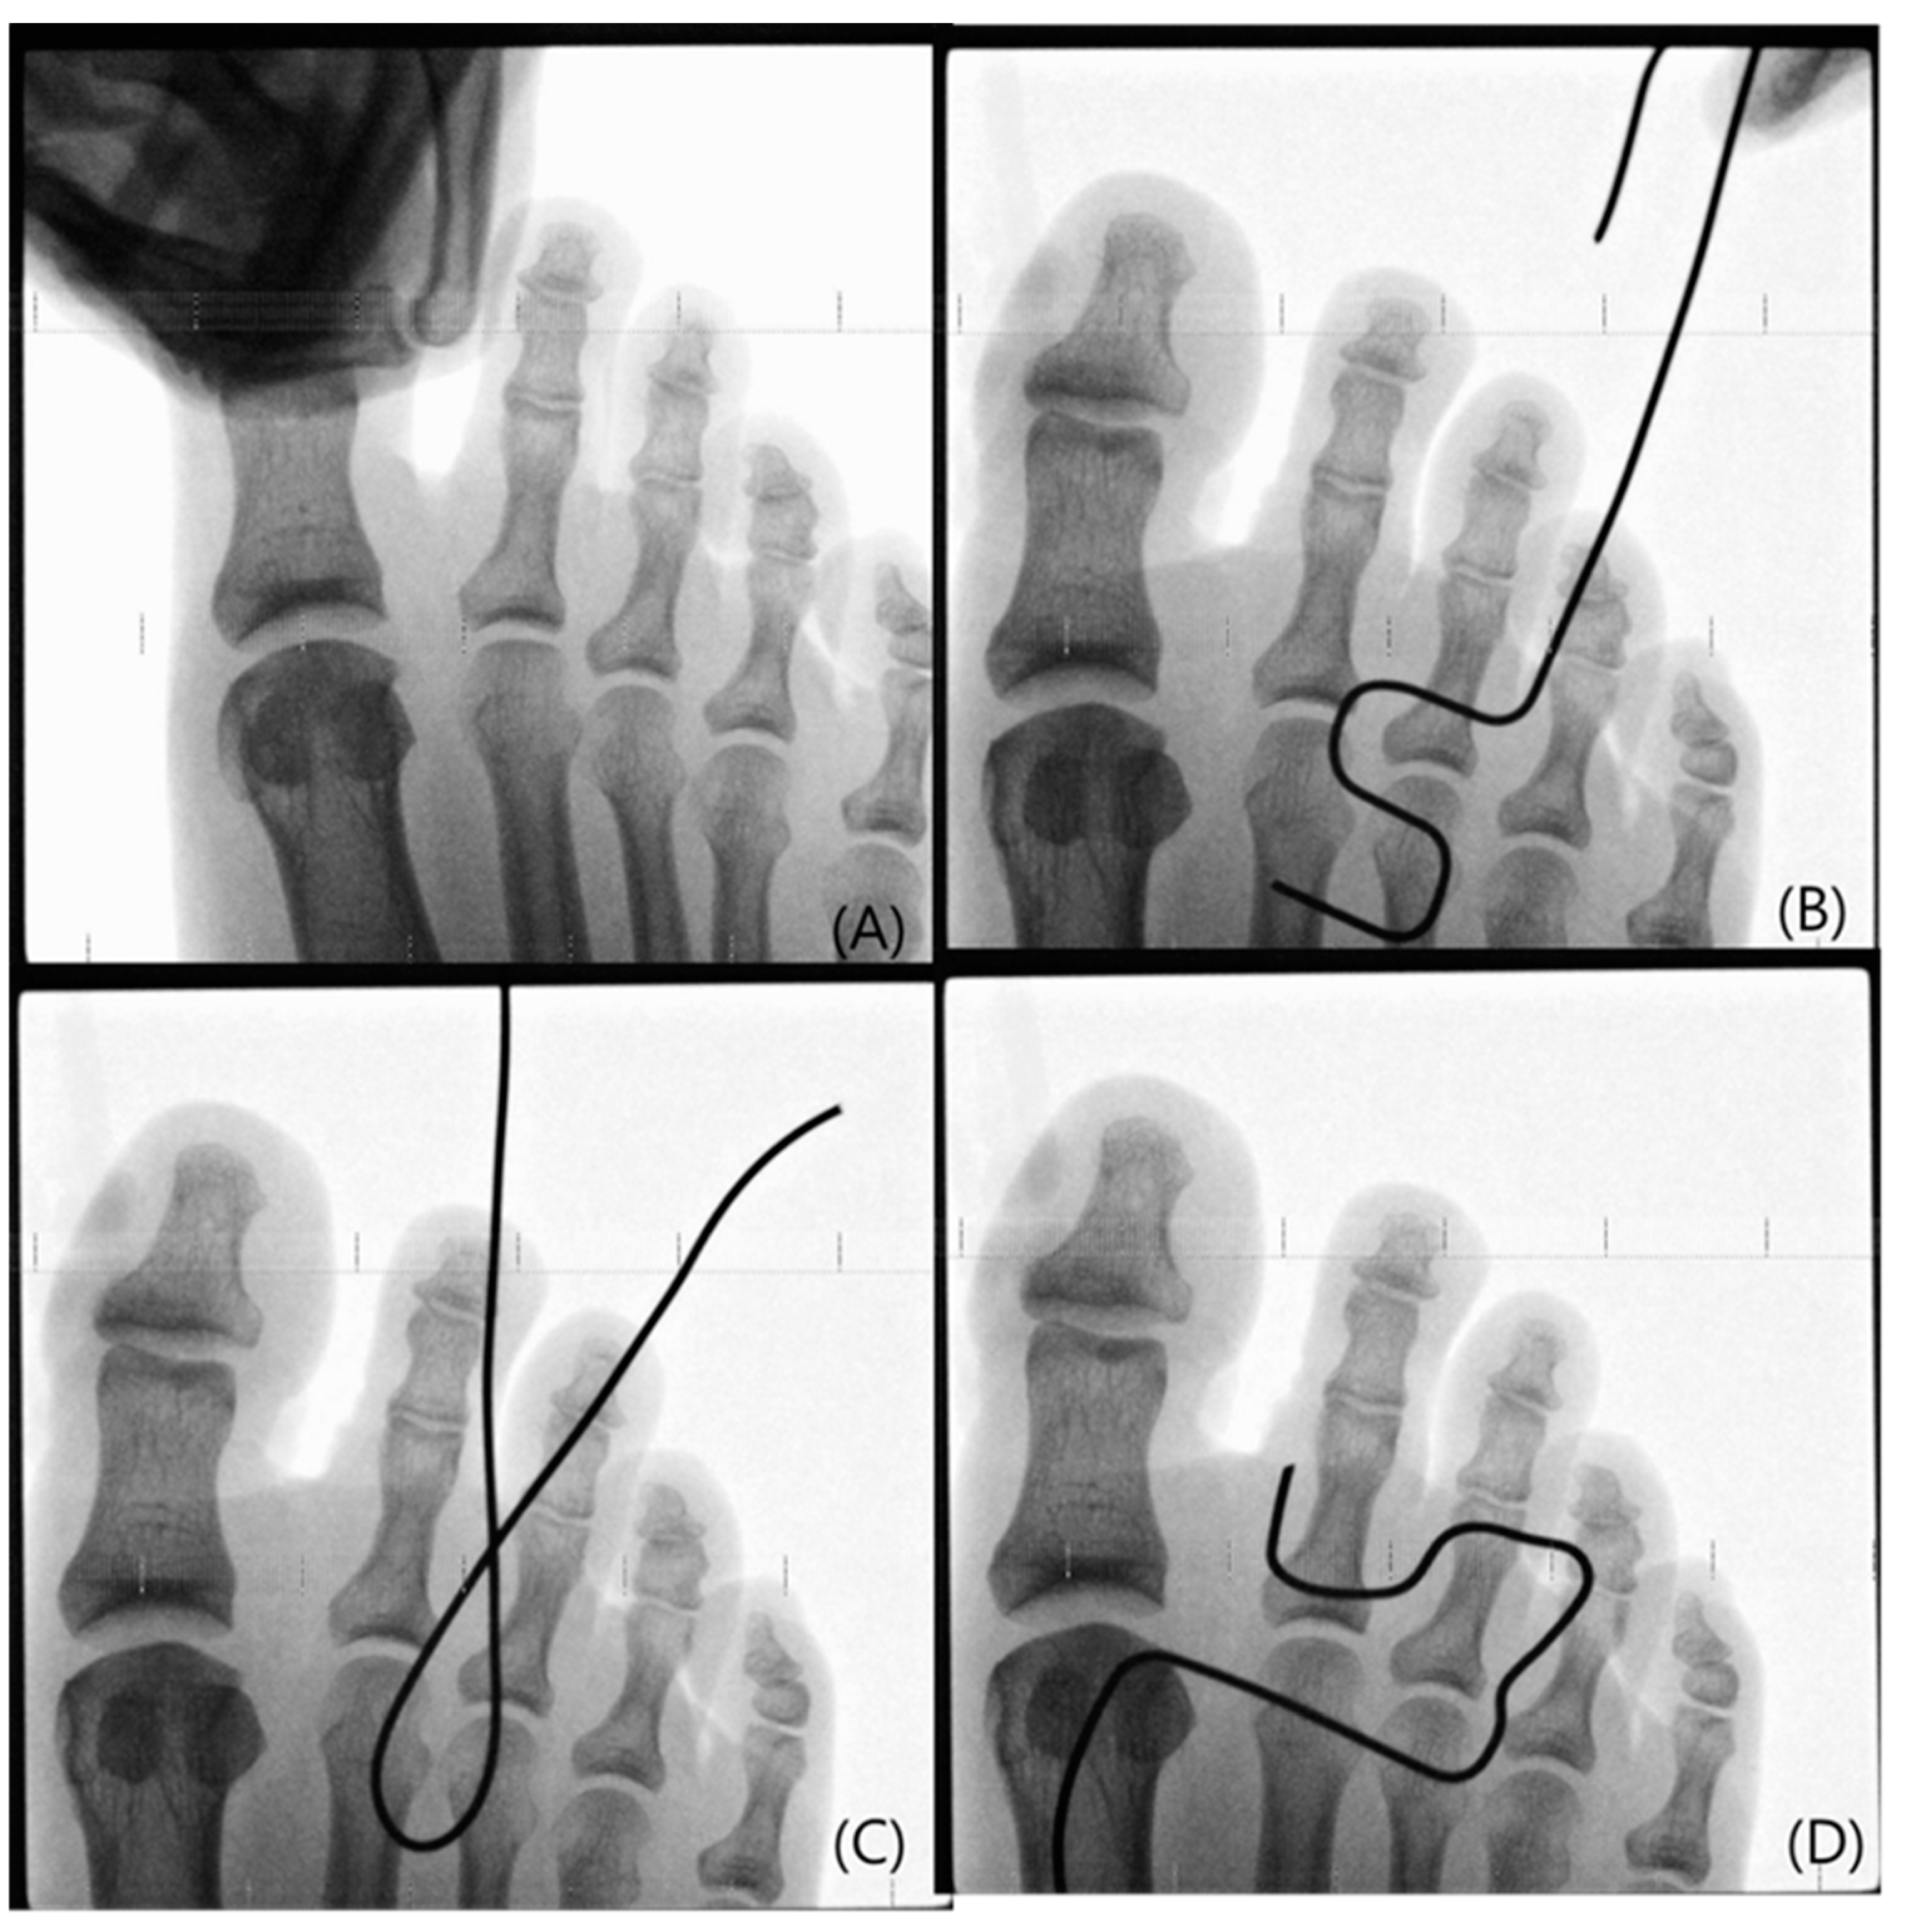

2.2. Methods